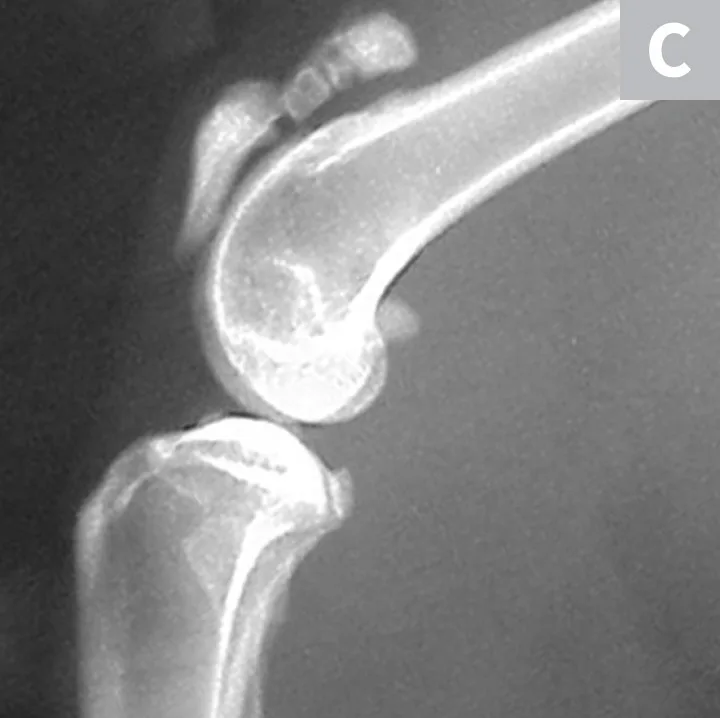

Serial radiographs of the pelvic limbs were taken periodically to monitor progression of the patellar fractures. Comparative orthopedic radiographs (Figure 3) 2 and 8 years after initial presentation revealed persistence of patellar fractures, with fragmentation, progressive sclerosis, and osteophytosis of the left patella.

Radiographs of the patellar fractures taken 2 years (A, left stifle; B, right stifle) and 8 years (C, left stifle; D, right stifle) after initial presentation. Progressive fragmentation and osteophytosis of the left patella and displacement of the right patellar fragments can be seen.